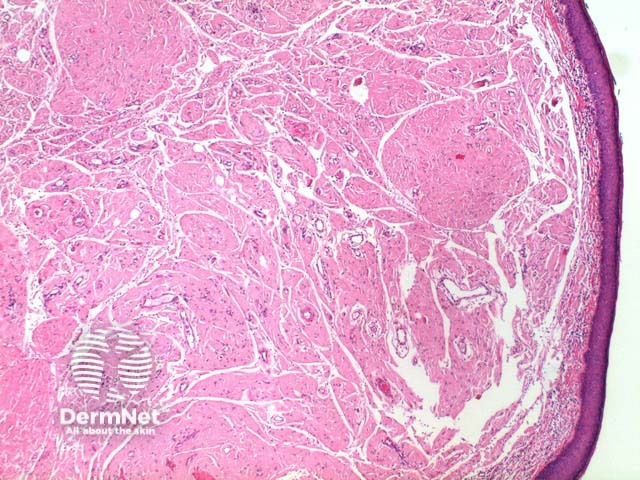

The scanning power view reveals a tumoral deposit within the dermis (figure 6). This may extend into the subcutaneous tissue (figures 7, 8, 9). Prominent clefting can be seen making superficial cases difficult to differentiate from colloid milium and paracolloid. The presence of numerous plasma cells in the accompanying inflammatory infiltrate, commonly with scattered Russell bodies, is helpful (figure 10).

Figure 6

Figure 7

Figure 8

Figure 9